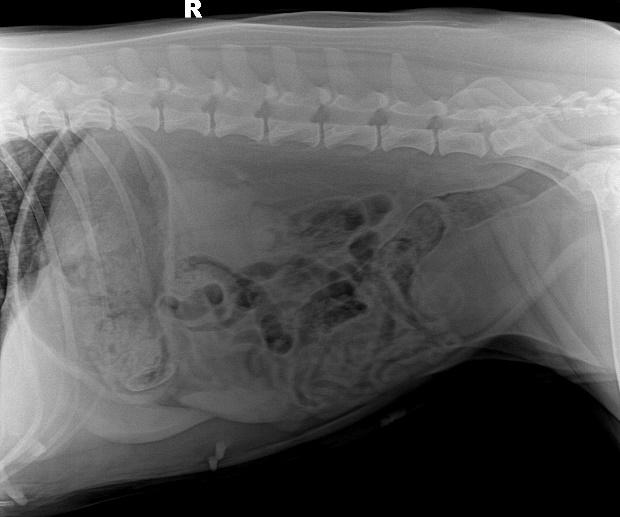

b. X射线检查:对于阻线性较强的物质(如金属、骨头)较容易辨别,对于阻线性与策划密度相似的物体较难确定,但是可以通过消化道灌服造影剂判断是否有阻塞或可包裹物体。

胃的正常大小:胃位于前腹部,隔和胆脏之后。胃排空时位于肋弓以内;从腹底算起,胃的腹侧缘大约在腹腔深度的1/3处。胃充盈时,胃向后向下延伸,与横结肠和腹底部相接。

摆位对

胃内异物(金毛,手术取出6cm大衣扣子)

钡餐4小时后胃内未排空(家猫,线性异物)